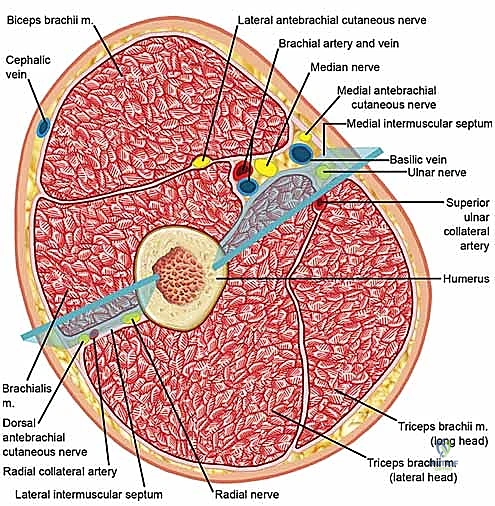

The arm is divided into two primary fascial compartments by the medial and lateral intermuscular septa, which extend from the deep investing fascia to the supracondylar ridges of the humerus.

The anterior compartment contains the primary flexors of the elbow: the biceps brachii, brachialis, and coracobrachialis. Crucially, it also houses the brachial artery, the median nerve, and the musculocutaneous nerve. The posterior compartment contains the triceps brachii muscle.

When decompressing the arm, the surgeon must be acutely aware of the radial nerve's trajectory. It courses from the posterior compartment, spirals around the posterior humerus in the radial groove, and pierces the lateral intermuscular septum approximately 10 cm proximal to the lateral epicondyle to enter the anterior compartment. Iatrogenic injury to the radial nerve during lateral septal release is a known and devastating complication.